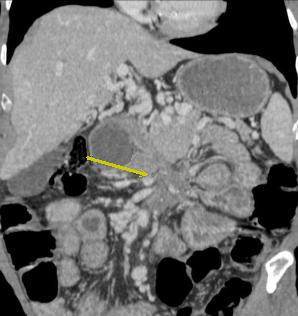

| Adenocarcinoma du duodenum a

extension locale vers le pancreas ( fleche rouge ) .

Dilatation du duodenum en amont |

Image TDM en coupe

coronale : Tumeur addeno carcinoma du jejunum

proximale a extension ganglionaire ( fleche rouge )

. Dilatation du jejunum en amont et aval . |